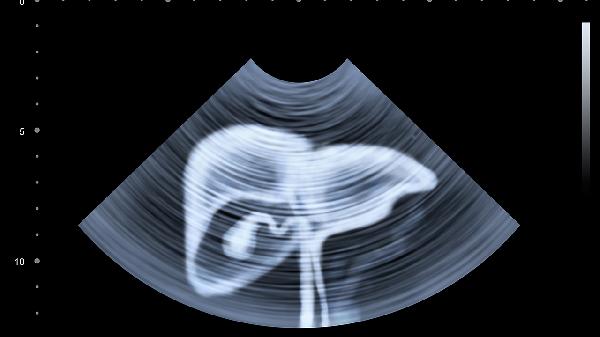

肝臟疾病的確診需要依賴更精準(zhǔn)的檢查。血清谷丙轉(zhuǎn)氨酶和谷草轉(zhuǎn)氨酶升高直接反映肝細(xì)胞損傷。堿性磷酸酶和γ-谷氨酰轉(zhuǎn)移酶異常提示膽汁淤積。凝血功能異常、白蛋白降低等指標(biāo)可評估肝臟合成功能。超聲、CT等影像學(xué)檢查能觀察肝臟形態(tài)結(jié)構(gòu)變化。對于慢性肝病患者,肝臟彈性檢測和肝活檢具有更高診斷價(jià)值。